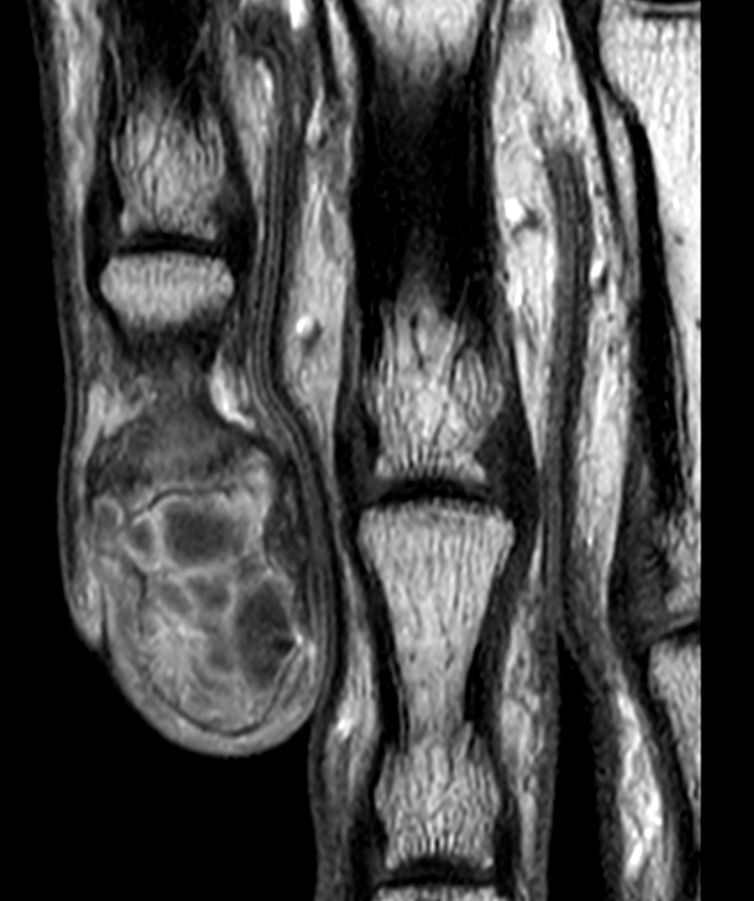

Patient with giant cell tumor in his finger. ExamCard includes Compressed SENSE to shorten exam time and 4D-TRAK XD for fast, dynamic contrast-enhanced MR Angiography with high spatial and temporal resolution simultaneously.

4D-TRAK XD Compressed SENSE